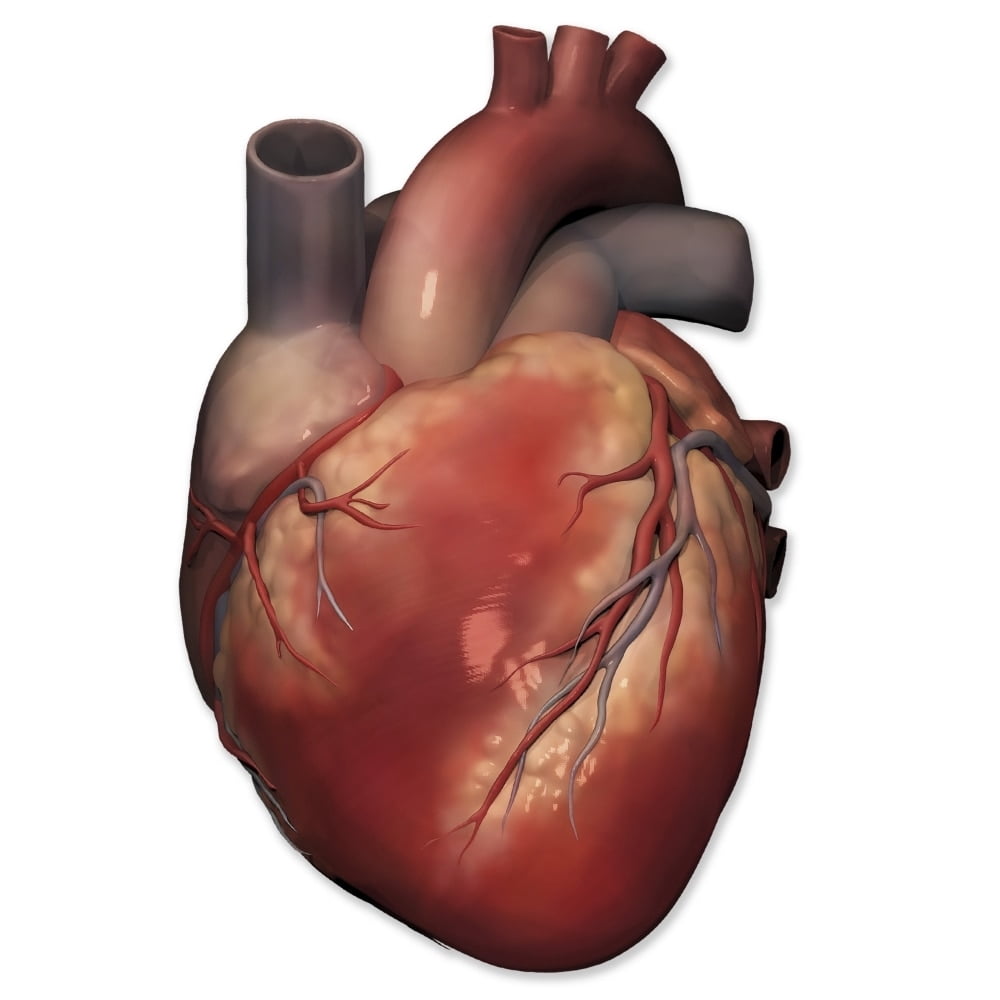

Anterior view of human heart anatomy Poster Print by Photon Illustration/Stocktrek Images  Cartoon Anatomical Heart

Human Heart Images Real - img-extra  //thebrainstormlab.com/banners/ami_banner.jpgThis is a medical | Heart anatomy drawing, Human

Human Heart 3D model realtime | CGTrader  Heart - Human Anatomy - PDF Zentangle Coloring Page | Human heart drawing, Human heart art